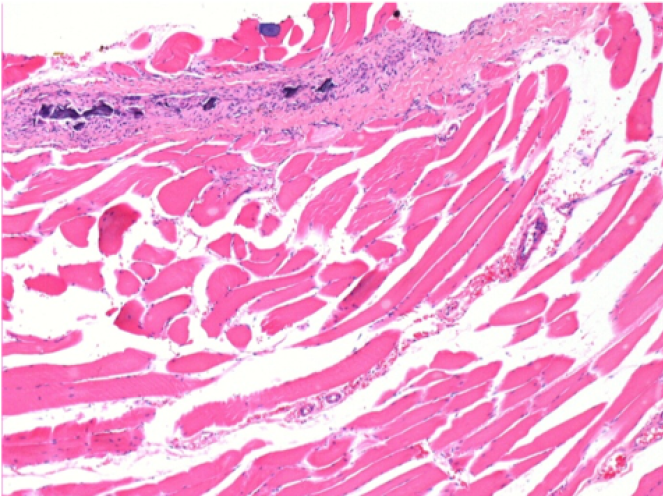

07

1 mese dopo Iniezione Endopeel

Scatola Nr 3

1 mese dopo Iniezione 0.1ml di Endopeel nel muscolo pretibiale destro ( Dx) .

Che cosa viene visualizzato in nero nella figura Sx : 100x-Giorno30 non é una necrosi come potrebbe immaginare un dilettante.

In effetti, 4 conclusioni devono essere prese in considerazione

- un artefatto di colorazione

- un`assenza di necrosi

- un`apoptosi

- un processo biorigenerativo

Sx : Controllo-100x-Giorno30

Dx:100x-Giorno30

Dx :400x-Giorno30